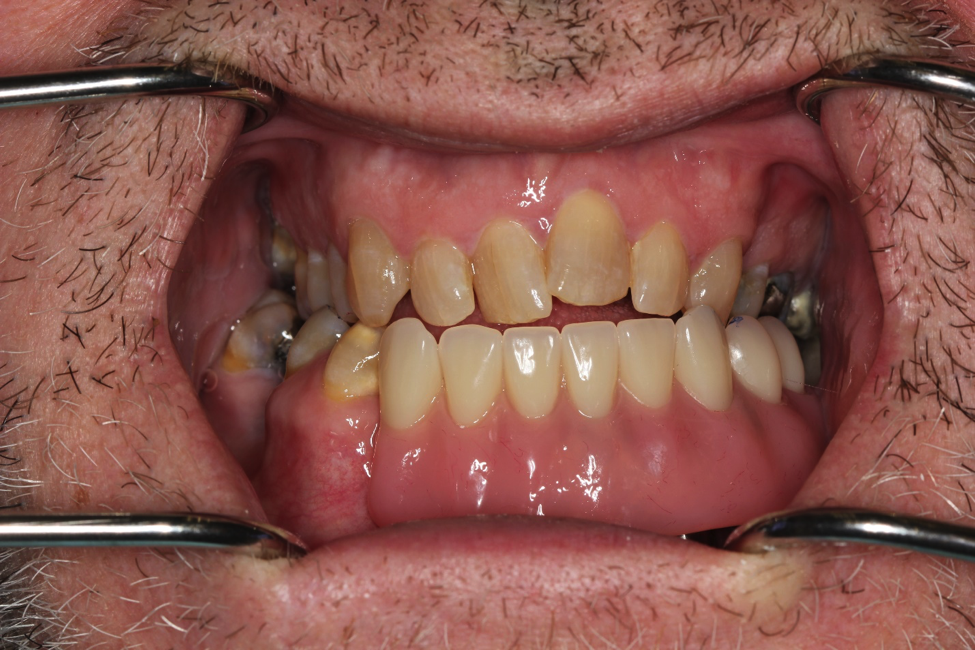

This patient had to undergo jaw surgery and he lost a lot of his teeth and bone. We managed to place implants in his bottom jaw and restore him with an implant-supported denture to give him his lost teeth, bone, and tissue back. This was a very challenging case from start to finish!